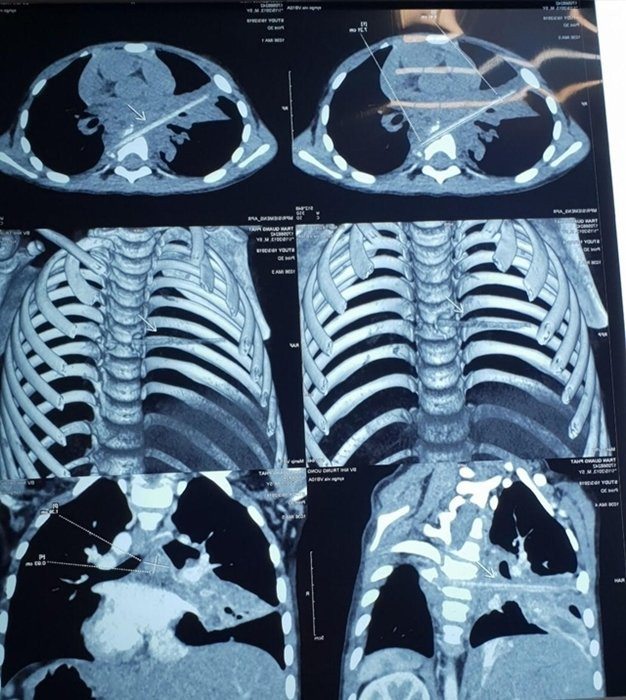

Qua các xét nghiệm và phim chụp, bác sĩ phát hiện có hình ảnh vôi hóa cột sống và viêm phổi thùy bên phải. Ngoài ra, trong mô phổi thùy bên phải của bệnh nhi có một dị vật dài, nhọn, khả năng cao đây chính là nguyên nhân khiến cho tình trạng viêm phổi của bệnh nhi không thuyên giảm.

Thông tin về ca bệnh, bác sĩ Trương Việt Nga, Bác sĩ chuyên khoa Hô Hấp, Bệnh viện Nhi Trung ương cho biết: “Bệnh nhi có tiền sử viêm phổi tái diễn. Từ phim chụp cắt lớp, chúng tôi phát hiện bệnh nhi có một dị vật dài, nhọn, kích thước khoảng 72x4mm tại nhu mô thùy phổi ở thùy giữa phổi phải.

Dị vật này đâm từ trước qua sau, xuyên qua khe giữ 2 thân đốt sống 6 và 7, làm vỡ thân đốt sống. Chính dị vật này là nguyên nhân khiến bệnh nhi bị viêm phổi không khỏi, suốt 8 tháng qua.